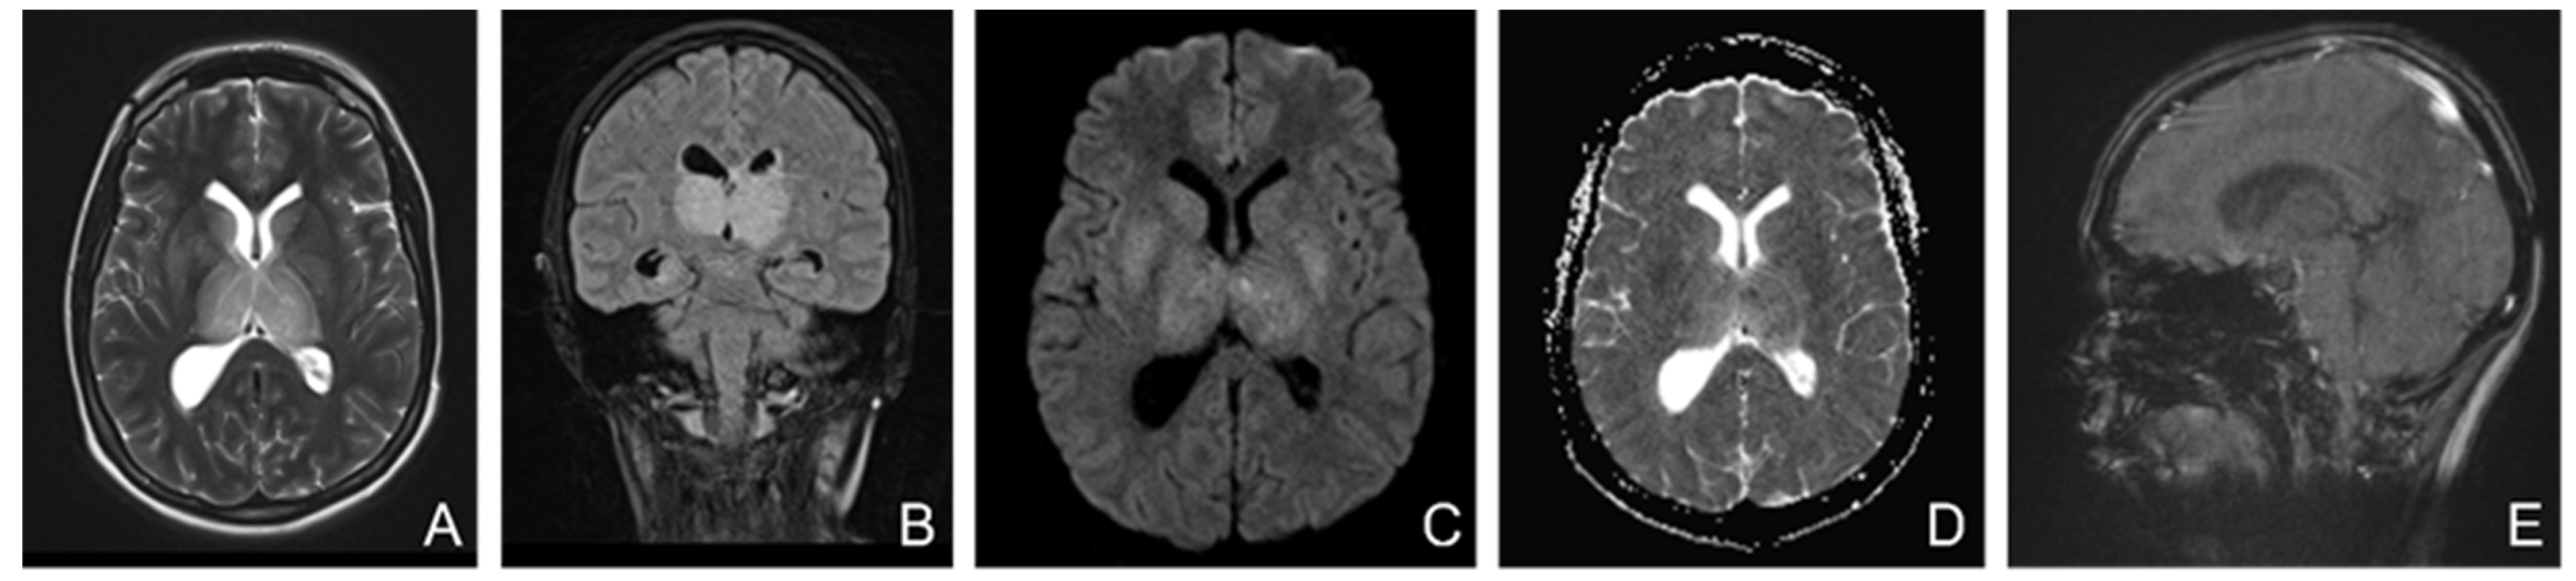

A brain MRI (Figure 5) showed flow asymmetry at the level of the cavernous sinuses, left more than right, coupled with fluid accumulation in the left mastoid cells, whilst cerebral parenchyma had morphology and signals within normal limits, thus establishing the diagnosis of bilateral (left > right) cavernous sinus thrombosis. The patient was started on continuous heparin infusion followed by treatment with acenocoumarol.

Figure 5. Non-enhanced MRI (at onset): ((A)—T2 axial, (B)—T1 sagittal, (C)—T2* axial, (D)—venous TOF coronal) shows unremarkable parenchyma and absence of flow in cavernous sinuses on TOF imagesFive months later, the patient came back to our clinic complaining of paroxysmal episodes of altered state of consciousness with language disorders such as verbal barrage followed by disorientation. An EEG was performed, showing a low-voltage background path, weakly modulated in spindles in the left derivations, reactive when opening the eyes, and rare isolated degraded peak-wave complexes, thus concluding that the patient was experiencing focal onset impaired awareness seizures; she was then started on antiepileptic treatment with oxcarbazepine 300 mg twice daily. She also was psychiatrically examined due to emotional lability confirming the diagnosis of depression and allowing antidepressant treatment to be started.